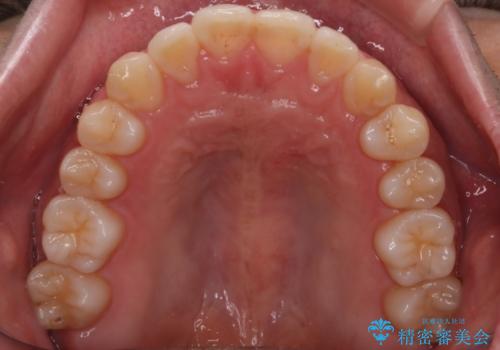

- 前歯のがたつきを主訴に来院されました。初診時、右上2番の口蓋側転位と右下7番の舌側傾斜が認められました。

インビザラインにてIPRと歯列弓拡大を行い、ゴム掛けで噛み合わせを改善する治療計画を立てました。

マウスピースの使用時間が短いため、シュミレーション通り進むか不安でしたが

治療期間1年で、主訴である前歯のがたつきを改善出来、

奥歯の噛み合わせも良くなりました。